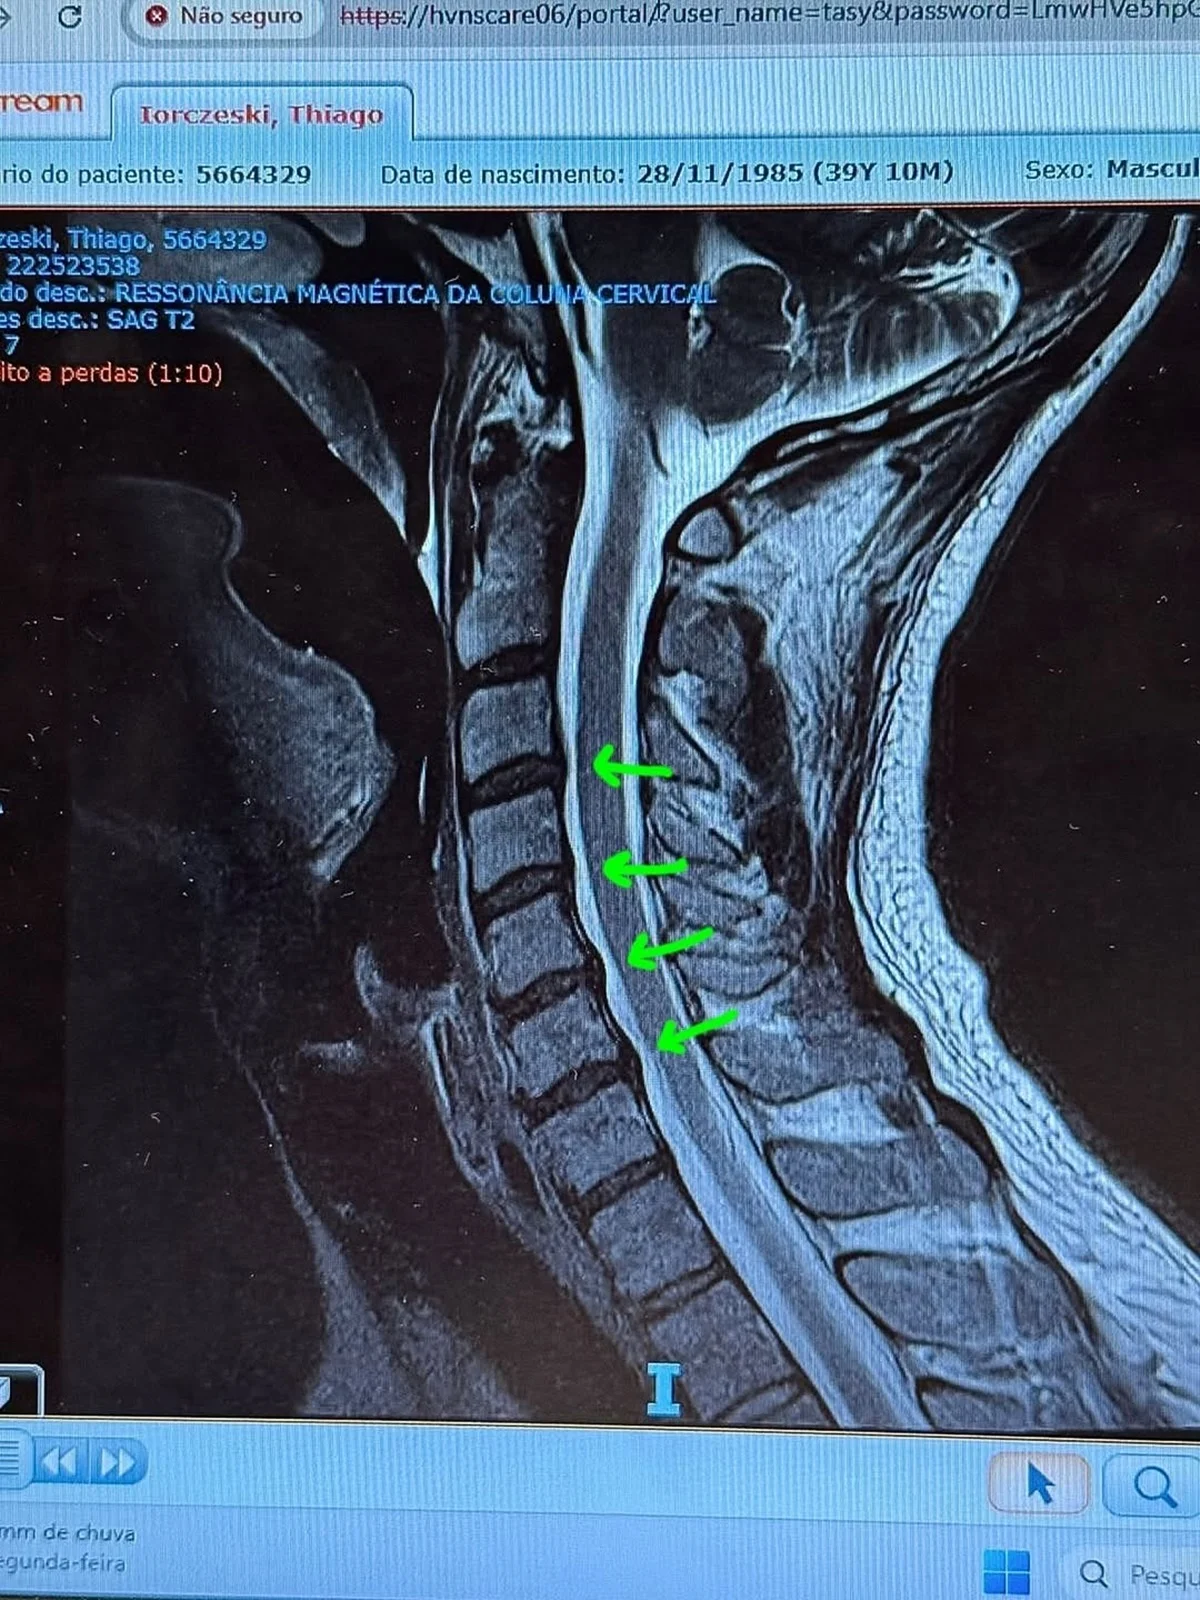

Tiago Iorc mostrou os exames que fez na unidade de saúde

Instagram/Reprodução 3 de 5

O cantor Tiago Iorc recorreu às redes sociais para acalmar os fãs após ser levado às pressas ao hospital em razão de uma crise de hérnia de disco na cervical. Nesta segunda-feira (13/10), ele compartilhou que está se sentindo melhor e com dores mais controladas. O artista passou por um procedimento de bloqueio do processo inflamatório, com a aplicação de injeções diretamente na coluna.

O cantor explicou que a crise foi resultado de anos mantendo hábitos prejudiciais à postura, como tocar violão por longos períodos e ficar com o pescoço curvado no celular. “Tive que ser internado às pressas por conta de uma crise de hérnia de disco na cervical, causada por má postura ao longo dos anos”, relatou.